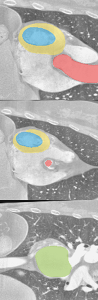

In image segmentation, the task is to classify each input pixel of an image to a label. In the medical domain, the labels can be different organs or different parts of them. Image segmentation is an important subtask of many other image understanding tasks, and therefore high reliability is very much desired.

Organ segmented into different parts; source: [2]